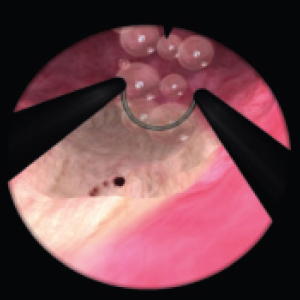

Diagnostic and surgical skills in Hysteroscopy & TUR

Resectoscope for hysteroscopy

Real resectoscope handle. Pedals for coagulation and electric dissection.

Magnetic feedback

Our proprietary magnetic feedback system allows for unprecedented immersion. Furthermore, unlike mechanical feedback systems, it is far more reliable.